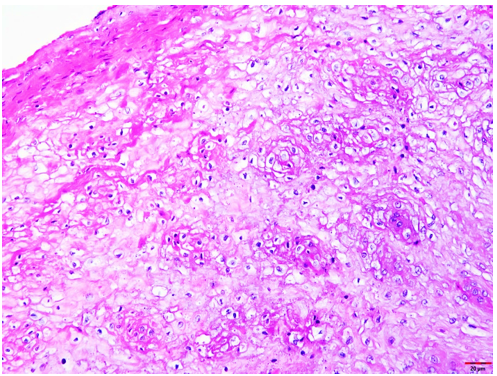

A 78-year-old male patient initially presented to the Dental College of Georgia at Augusta University for periodontal implant therapy and prophylaxis appointments. During clinical examination, several incidental clinical findings such as xerostomia, coated tongue, abnormal bilateral white lesions, and hyper-keratinization on the lateral borders of the tongue (Figure 1) and buccal mucosa (Figure 2) were noted. These findings were consistent with patient’s known history of Pachyonychia Congenita, previously affecting his skin, nails (Figure 3), and mucous membranes.

The formalin-fixed tissue specimen was subjected to routine processing after which 5μm sections were cut and stained with hematoxylin and eosin. The tissue sections showed hyperkeratinized surface mucosal epithelium supported by lamina propria (Figure 4). The epithelium was covered by a thick layer of parakeratin. The spinous cell layer was thickened and showed superficial layers of cells exhibiting prominent deeply chromatic nuclei surrounded by vacuolated cytoplasm imparting optically clear cells (Figure 5). The basal and suprabasal layers of cells exhibited the normal cellular maturation pattern without any cellular or nuclear atypia (Figure 6). Subepithelial inflammatory cell infiltrates were noted in the superficial lamina propria. A diagnosis of “Hyperparakeratosis with prominent perinuclear vacuolization of the epithelium”, consistent with Pachyonychia congenita was made.

Figure 2: Hyperkeratosis on the buccal mucosa

Figure 5: Tissue section exhibiting the thickening of the spinous cell layer with superficial layers of cells exhibiting prominent deeply chromatic nuclei surrounded by vacuolated cytoplasm imparting optically clear cells